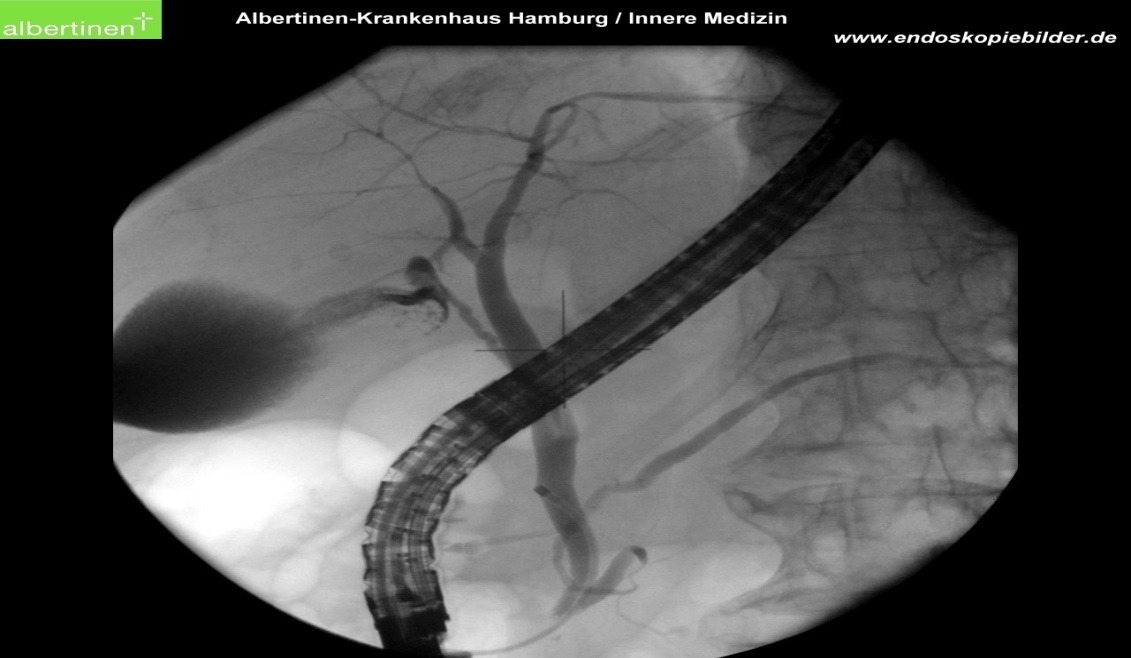

ERCP,即经内镜逆行胰胆管造影术,是将十二指肠镜插至十二指肠吻合部,然后插入导管,在X线透视下注射造影剂造影、导入子内镜/超声探头观察,使胰、胆管造影剂显影的技术,是目前微创治疗胆、胰疾病的主要手段之一。ERCP最大的优势就是微创,即不开刀,病人腹部没有伤口,又叫不开刀的内镜下手术,而且术后大部分病人恢复的非常快,无明显疼痛,一般住院2-3天就可以出院,而且治疗费用低,易于被广大患者接受。

患者李xx,64岁,10多年前因胆囊结石、肝内胆管结石行肝叶切除、胆囊切除,今年10月份又在外院确诊为直肠癌、胆管多发结石,因直肠癌直接危及生命,李XX一家紧急在外院先行直肠癌手术,术后恢复良好,但由于肿瘤分期偏晚,已经有淋巴结转移。经我院李宝秀副院长义诊会诊后建议从赫章转我院行术后辅助化疗,择期辅助放疗。该患者于一周前收治于我院综合内科,完善全面检查评估化疗耐受性后,李宝秀副院长指出:患者有胆总管多发顽固结石,可患者化疗周期长,且化疗对患者免疫力影响较大,化疗期间容易反复发生胆管炎,可能给患者带去巨大的病痛。同时考虑患者多次手术史,再次开腹手术耐受力差,并且术后恢复时间长,并发症多,不利于患者按时行化疗,建议患者行“ERCP取石术”。在患者及家属充分知情同意后,我院综合内科联合麻醉科、影像科,多学科通力合作,手术于2021年12月7日在全麻下顺利进行,历时4小时,共取出了9枚巨大的结石(其中5枚进入肠道,随肠道排出),其中最大的一枚直径约2.5cm。术后患者恢复良好,无明显疼痛,患者及家属对手术效果高度满意。